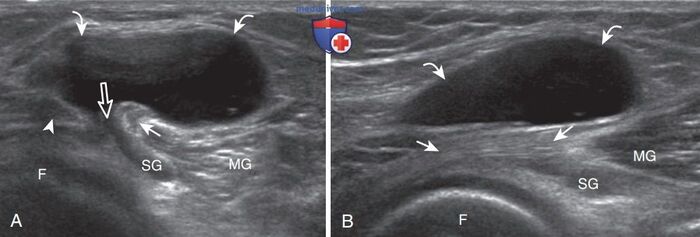

УЗИ - самый доступный и безопасный метод, саму кисту прекрасно видно.

МРТ, когда нужно заглянуть дальше, например, чтобы исключить повреждение заднего рога мениска или крестообразных связок - такие глубоко залегающие структуры по УЗИ не видно.

Иногда в полости кисты можно найти какие-нибудь образования, которые мигрировали из полости сустава (кальцинаты, костные тела, хрящевые тела, костно-хрящевые).